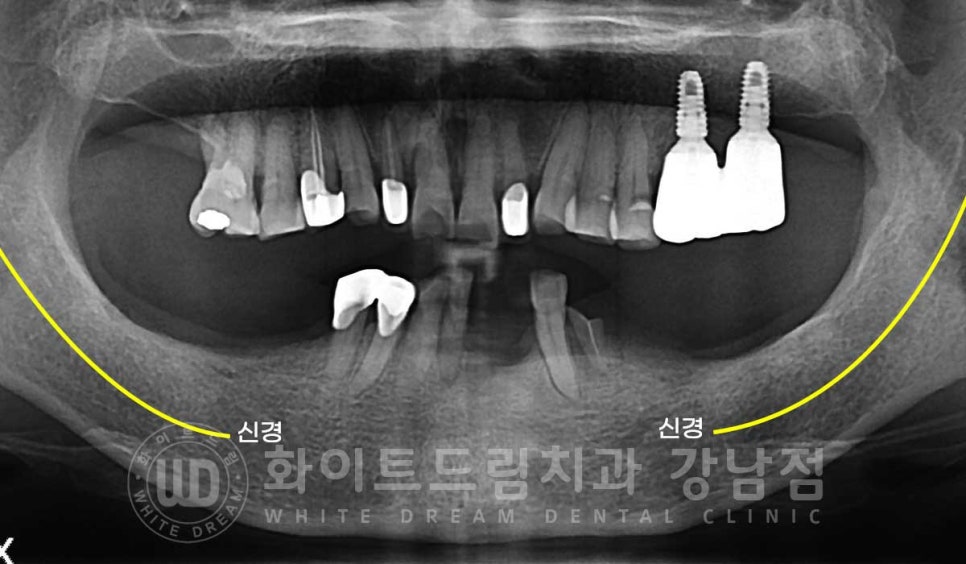

하악 임플란트는 하악 턱뼈 안을 지나가는 신경을 항시 주의하며

치료를 진행해야 합니다.

치조골이 흡수되면서 신경관과의 거리도 가까워지기에

사전에 3D-CT를 통해 위치를 정확하게 확인한 후 치료에 들어가게 됩니다.

치조골 흡수로 인해 신경관과의 거리가 생각보다 가까울 경우에는

충분한 길이의 임플란트보다는

짧은 임플란트를 식립하거나 식립 위치를 변경하게 되는 상황까지

발생할 수 있답니다.

다행히 환자분은 이 정도까지의 골흡수는 아니어서 뼈이식을 동반한 임플란트 식립을 진행했답니다.